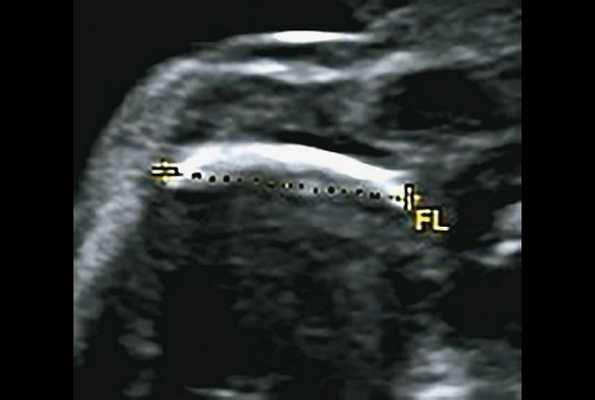

в) Изогнутая и укороченная бедренная кость.

г) Изогнутая и укороченная бедренная кость.

Основные ультразвуковые характеристики плодов, полученные при нашем исследовании, отображены в таблице 1 и на рис. 1-4.

| Срок беременности | Голова | Грудная клетка | Конечности | Дополнительные находки |

|---|---|---|---|---|

| Набл. 1. 24,3 нед. | БПР - 25,3 нед. ОГ - 24,6 нед. Аномально повышенная бороздчатость и выпуклость извилин нижнемедиальной поверхности височных долей (рис. 1а). | Торакоабдоминальное соотношение - 66,7% (рис. 1б) Длина ребра - среднее для 16 нед. | Бедренная кость 19,6 мм (47,8% от должной), изогнута ("телефонная трубка") (рис. 1в). Остальные кости - среднее для 15 нед. | Уплощенные тела поясничных позвонков. |

| Набл. 2. 20,3 нед. | БПР - 21,5 нед. ОГ - 20,3 нед. Уплощенный затылок. Выпуклые темпоральные бугры (рис. 2а). Аномально повышенная бороздчатость и выпуклость извилин нижнемедиальной поверхности височных долей (рис. 2б). | Торакоабдоминальное соотношение - 63,3% (рис. 2в) Окружность груди - среднее для 18 нед. Длина ребра - среднее для 15 нед. | Бедренная кость 17,7% (61% от должной), изогнута ("телефонная трубка") (рис. 2г). Остальные кости - среднее для 13-14 нед. | Гипоплазия костей носа. |

| Набл. 3. 24 нед. | БПР - 30 нед. ОГ - 27,2 нед. Уплощенный затылок. Выпуклые темпоральные бугры (рис. 3а). Аномально повышенная бороздчатость и выпуклость извилин нижнемедиальной поверхности височных долей (рис. 3б). | Торакоабдоминальное соотношение - 56,6% (рис. 3в) Окружность груди - среднее для 20 нед. Сердце/грудь (см 2 ) - индекс 0,6. | Бедренная кость 23,1 мм (57% от должной), изогнута ("телефонная трубка") (рис. 3г) Остальные кости - 50% для 15-16 нед. Нормальная установка пальцев кисти (рис. 3д). | Многоводие. |

| Набл. 4. 26,5 нед? | БПР - 22,6 нед. ОГ - 22,6 нед. Форма - трилистник (рис. 4а). Боковые желудочки - 22 мм, высокий лоб, расширенный родничок, сагиттальный шов (рис. 4б). | Торакоабдоминальное соотношение - 65,7% (рис. 4в). Окружность груди - среднее для 23 нед. Колоколообразная форма. | ДБ - 23 мм (51% от должной). Остальные кости - 50% для 15-17 нед. Нормальная установка пальцев кисти (рис. 4б). | Уплощенные тела поясничных позвонков (рис. 4г). |

Примечание. БПР - бипариетальный размер, ОГ - окружность головы, ДБ - длина бедренной кости.

Длину бедренной кости оценивали по региональным нормативам, а остальные кости - по Ph. Jeanty. Окружность грудной клетки оценивали по U. Chitkara и соавт. [14], длину ребер - по A.Z. Abuhamad [15].

В наблюдениях 1-3 наличие изогнутой бедренной кости (по типу "телефонной трубки") (рис. 1в, 2г, 3г) позволяло предположить наличие ТД I типа. Целе направ ленное исследование головного мозга этих плодов в дополнение к описанным скелетным признакам показало и картину ДВД. Была выявлена аномально повышенная бороздчатость и выпуклость извилин нижнемедиальной поверхности височных долей у плодов в наблюдениях 1-3 (рис. 1а, 2б, 3б). Это позволило установить диагноз ТД I типа.

УЗИ позволяет выделить группу скелетных дисплазий плода с сужением грудной клетки, являющимся одним из важных прогностически неблагоприятных признаков независимо от нозологической формы остеохондроплазий. Во всех представленных нами случаях у плодов отмечены микромелия и гипоплазия грудной клетки (окружность грудной клетки была менее 5% для гестационного срока, а торакоабдоминальное соотношение было в пределах 56,6-67,6%).

В остальных трех наблюдениях деформация укороченных бедренных костей на фоне характерных признаков остеохондроплазий позволила предположить ТД I типа. В то же время эти наблюдения требовали проведения дифференциальной диагностики с рядом скелетных дисплазий.

Наиболее важным, с точки зрения A.M. Bircher и соавт. [16], является необходимость дифференцировки ТД с ахондроплазией, так как последняя является частой и совместимой с жизнью скелетной дисплазией. При этом наиболее эффективным дифференциальным признаком предлагается степень укорочения бедренной кости: невыраженное укорочение (ДБ составляет до 80% от должной) характерно для ахондроплазии, тогда как при ТД укорочение выраженное (ДБ составляет 30-60%). В наших наблюдениях укорочение ДБ составляло 47-61% от должной. В работе A. Khalil и соавт. [17] показано увеличение диафизарно-метафизарного угла (более 130°) бедренной кости при ахондроплазии. С нашей точки зрения, в дифференциальной диагностике ТД с гомозиготной формой ахондроплазии решающую роль может играть семейный анамнез, а с гетерозигототной - наличие узкой грудной клетки. Кроме того, как видно по нашим наблюдениям, при ТД определяется правильная установка пальцев кисти (рис. 3д, 4б) в отличие от ахондроплазии, при которой определяется установка пальцев в виде "трезубца".